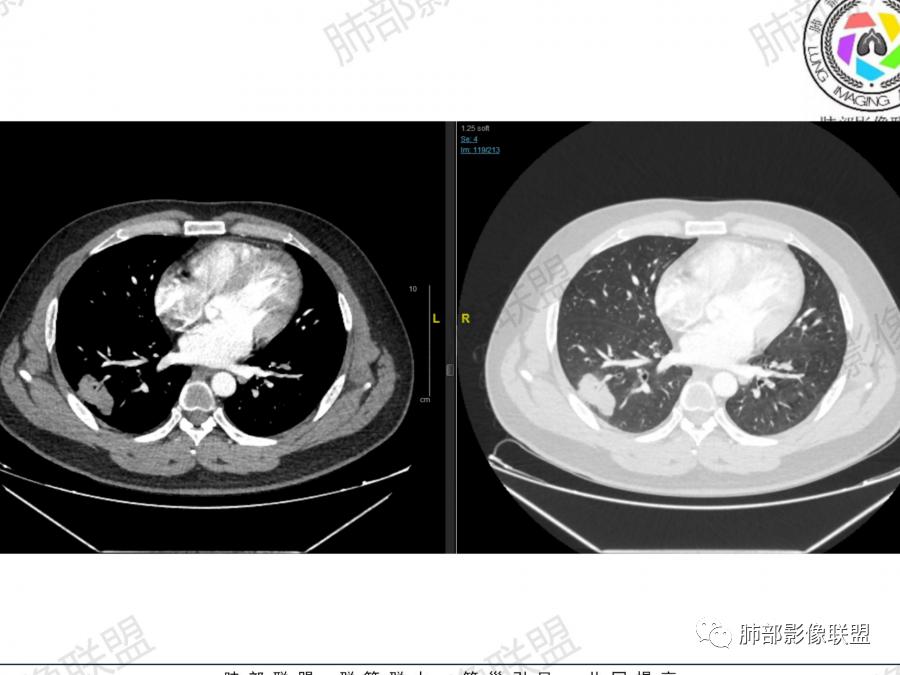

晨读:男,37岁,咳嗽气喘一月,加重两天。CT示右肺多发实变影,大者位于右肺上叶尖段,内可见空洞,局部内部可见残存肺组织,余结节位于胸膜下,强化均匀,内部可见血管穿行。首先考虑隐球菌感染可能,其次淋巴增殖类疾病

晨读,青年男性,咳嗽气喘病史,铁蛋白及D2聚体升高,右肺多发病灶,上叶团块影,深分叶,不均匀强化,可见血管征,支气管充气征,走形自然。右肺下叶背段球形阴影,有融合趋势,可见空洞,洞壁光滑,有血管自然通过,下叶外侧段靠近胸膜球形阴影,有血管进入,总体恶性证据多,淋巴瘤首选。

晨读:男性,37岁,咳嗽、气喘1月,加重2天。胸部CT:右肺上叶尖段、右下叶胸膜下和支气管树周围多发结节影、大片实变(由多结节融合形成),部分边界较清、部分周围模糊晕,病灶内悬浮空泡、支气管充气征、部分支气管进入后堵塞,血管漂浮,密度较均匀,综合考虑:隐球?鉴别淋巴增殖类病变。

主要征象:右肺多发病变  一元论?二元论?

1.右上肺团块:分叶,不均性强化,其内支气管走行自然,增强血管影可见、清晰。

疑问:空洞还是残余肺组织?

2.右下肺结节、实变:胸膜下,长轴平行胸膜。部分似有晕影。支气管进入后近段截断

2、右肺多发结节影,大者位于右肺上叶尖段,内可见空洞,空洞内壁欠规整,内可见分隔,余结节位于胸膜下、结节大小不等、形态相近,强化均匀,内部可见血管穿行,血管及支气管走行自然。结合临床及影像,符合隐球病。